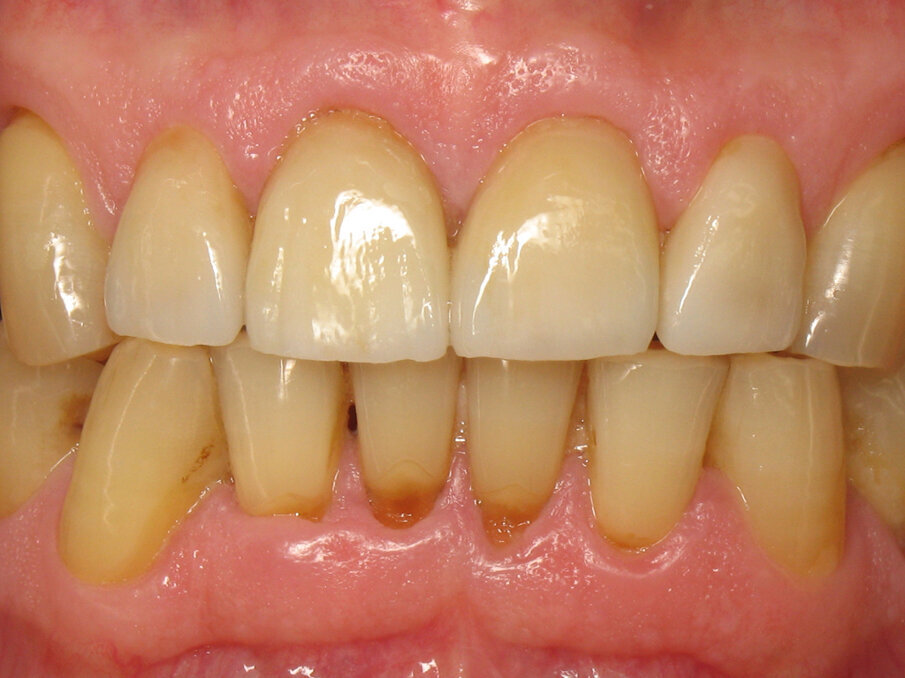

Figure 1 shows a clinical situation in which the patient will be able to smile literally and figuratively. The teeth have a harmonious shape, position and shade, despite minor defects such as cervical lesions of the mandibular incisors. There is also good periodontal health, there being no plaque or gingivitis. What the reader is far from suspecting is that this final situation corresponds to the placement of four crowns on teeth #12–22.

Captured at the same time as Figure 10, Figures 11 and 12 show the initial situation of this patient, who came for a consultation to rehabilitate his maxillary incisors. The diagnosis revealed nocturnal bruxism as the origin of several areas of crown destruction: wear of the incisal edge, abfraction, missing restorations, cracks and a complex coronary fracture. It is easy to understand why the choice of material was zirconia. It is also easy to understand the motivations of this patient to recover his lost smile. This degradation over time is inevitable, but in this patient, it was particularly fast and aggressive. Reversing the course of time was therefore obvious in restoring the dental health of this patient.